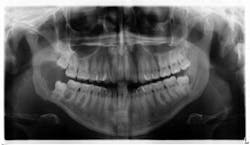

Figure 3: Radiograph from patient’s initial exam

A healthy 22-year-old female patient presented for a comprehensive examination (figure 3). She had no chief complaints and no caries. The patient was referred to an oral surgeon for removal of wisdom teeth. Following that, all contact was lost.